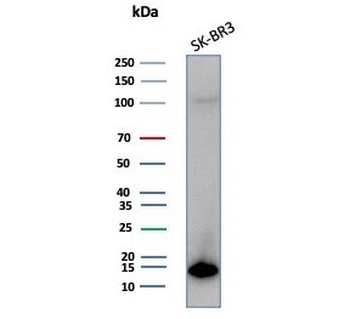

Cathepsin D Antibody

| Catalog Number | orb621663 |

|---|---|

| Category | Antibodies |

| Description | Cathepsin D Antibody |

| Species/Host | Rabbit |

| Clonality | Recombinant |

| Tested applications | FC, ICC, IHC, IP, WB |

| Reactivity | Human, Mouse |

| Antibody Type | Primary Antibody |

| Conjugation | Unconjugated |

| UniProt ID | P07339 |